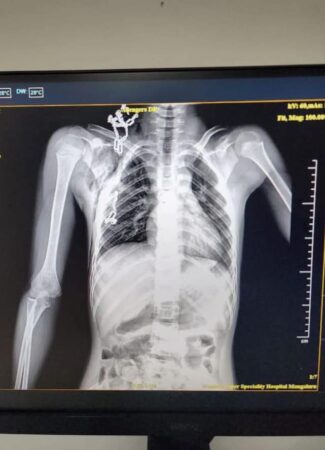

ಮಂಗಳೂರು: ವೆನ್ಲಾಕ್ ಆಸ್ಪತ್ರೆಯ ಹೃದಯ, ಎದೆ ಮತ್ತು ರಕ್ತನಾಳದ ಶಸ್ತ್ರಚಿಕಿತ್ಸೆ ವಿಭಾಗದ ಸಂಪೂರ್ಣ ತಂಡ, ಡಾ. ಸುರೇಶ್ ಪೈ ಅವರ ನೇತೃತ್ವದಲ್ಲಿ, 12 ವರ್ಷದ ಬಾಲಕನ ಎದೆಯಿಂದ ಒಂದು ದೊಡ್ಡ ತೆಂಗಿನ ಗರಿಯನ್ನು ಯಶಸ್ವಿ ಶಸ್ತ್ರ ಚಿಕಿತ್ಸೆಯ ಮೂಲಕ ಹೊರತೆಗಿದಿದ್ದಾರೆ.

ಮೂಲತಃ ಅಸ್ಸಾಂ ರಾಜ್ಯದ ಪ್ರಸ್ತುತ ಮಡಿಕೇರಿಯಲ್ಲಿ ಕೆಲಸದಲ್ಲಿದ್ದ ಬಾಲಕ ಬಿದ್ದು ಮರದ ತುಂಡು ಅವನ ಕುತ್ತಿಗೆಗೆ ಪ್ರವೇಶಿಸಿ ಎದೆಯಲ್ಲಿ ಸಿಕ್ಕಿಕೊಂಡಿತ್ತು. ಸಂಜೆ 7.30 ಕ್ಕೆ ಆಘಾತಕ್ಕೊಳಗಾದ ನಂತರ ಮಧ್ಯರಾತ್ರಿ 12.15 ಕ್ಕೆ ಮಂಗಳೂರಿನ ವೆನ್ಲಾಕ್ ಆಸ್ಪತ್ರೆಗೆ ಕರೆತರಲಾಯಿತು. ಮಧ್ಯರಾತ್ರಿ 1.30 ರಿಂದ 3.30 ರವರೆಗೆ ಶಸ್ತ್ರಚಿಕಿತ್ಸೆ ನಡೆಯಿತು. ಮರದ ತುಂಡಿನ ಜೊತೆಗೆ ಸ್ಟೀಲ್ ಚೈನ್ ಕೂಡ ಸಿಲುಕಿಕೊಂಡಿತ್ತು, ಮರದ ಗರಿ ಮತ್ತು ಸ್ಟೀಲ್ ಚೈನ್ ಶಸ್ತ್ರಚಿಕಿತ್ಸೆಯಿಂದ ಹೊರತೆಗೆದು ಯುವ ಜೀವವನ್ನು ಉಳಿಸುವಲ್ಲಿ ಸಿಟಿವಿಎಸ್ ವೈದ್ಯಕೀಯ ತಂಡದ ಅಸಾಧಾರಣ ಪ್ರಯತ್ನ ಮಹತ್ತರವಾಗಿದೆ.